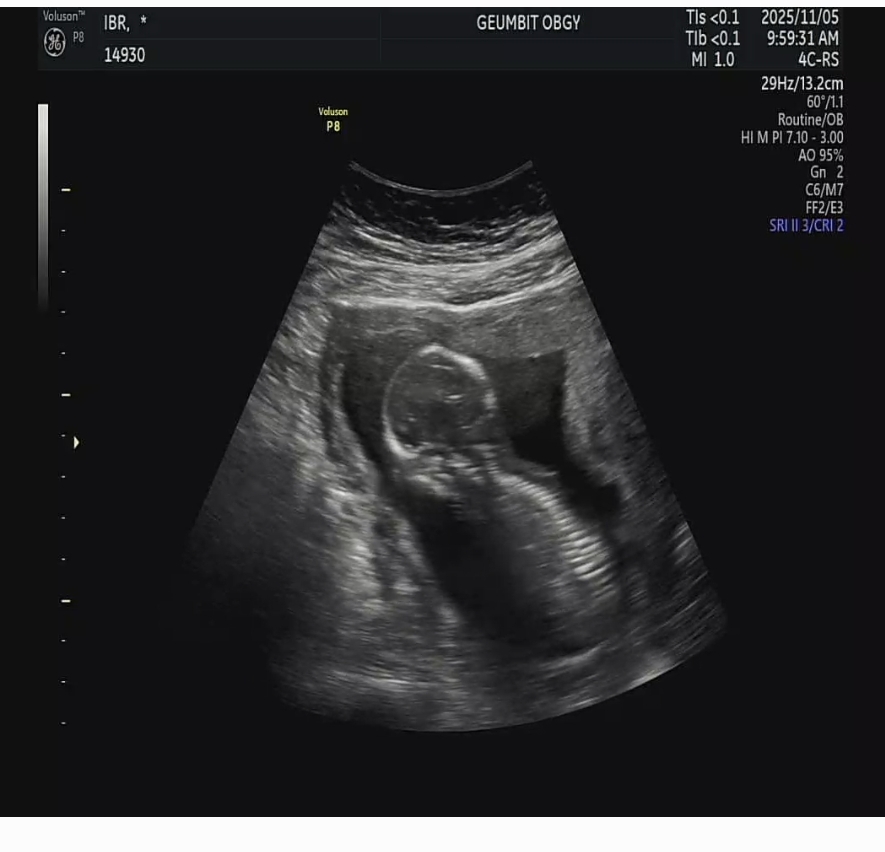

15주 3일차 초음파입니다. 애기가 하늘을 안보고 밑을 보고있는거같은데.. 이맘때 이럴수 있는건가요? 제가 초음파 잘 볼줄몰라 여쭤봅니다

네 등 척추뼈네요 저도 14 16주 초음파 보러갈때 다 엎드려있었어요. 그러다가 하늘보ㅏ서 설명 알았어요 걱정거리 아니더라구요